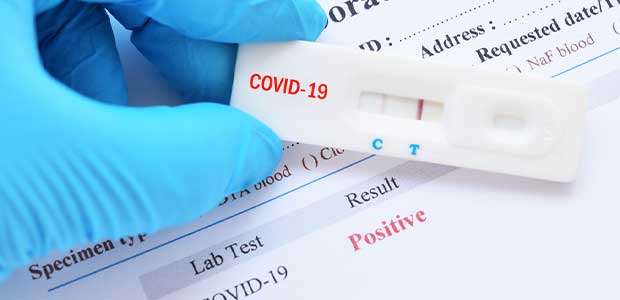

New guidelines published last week include what to do if you are exposed to COVID-19.